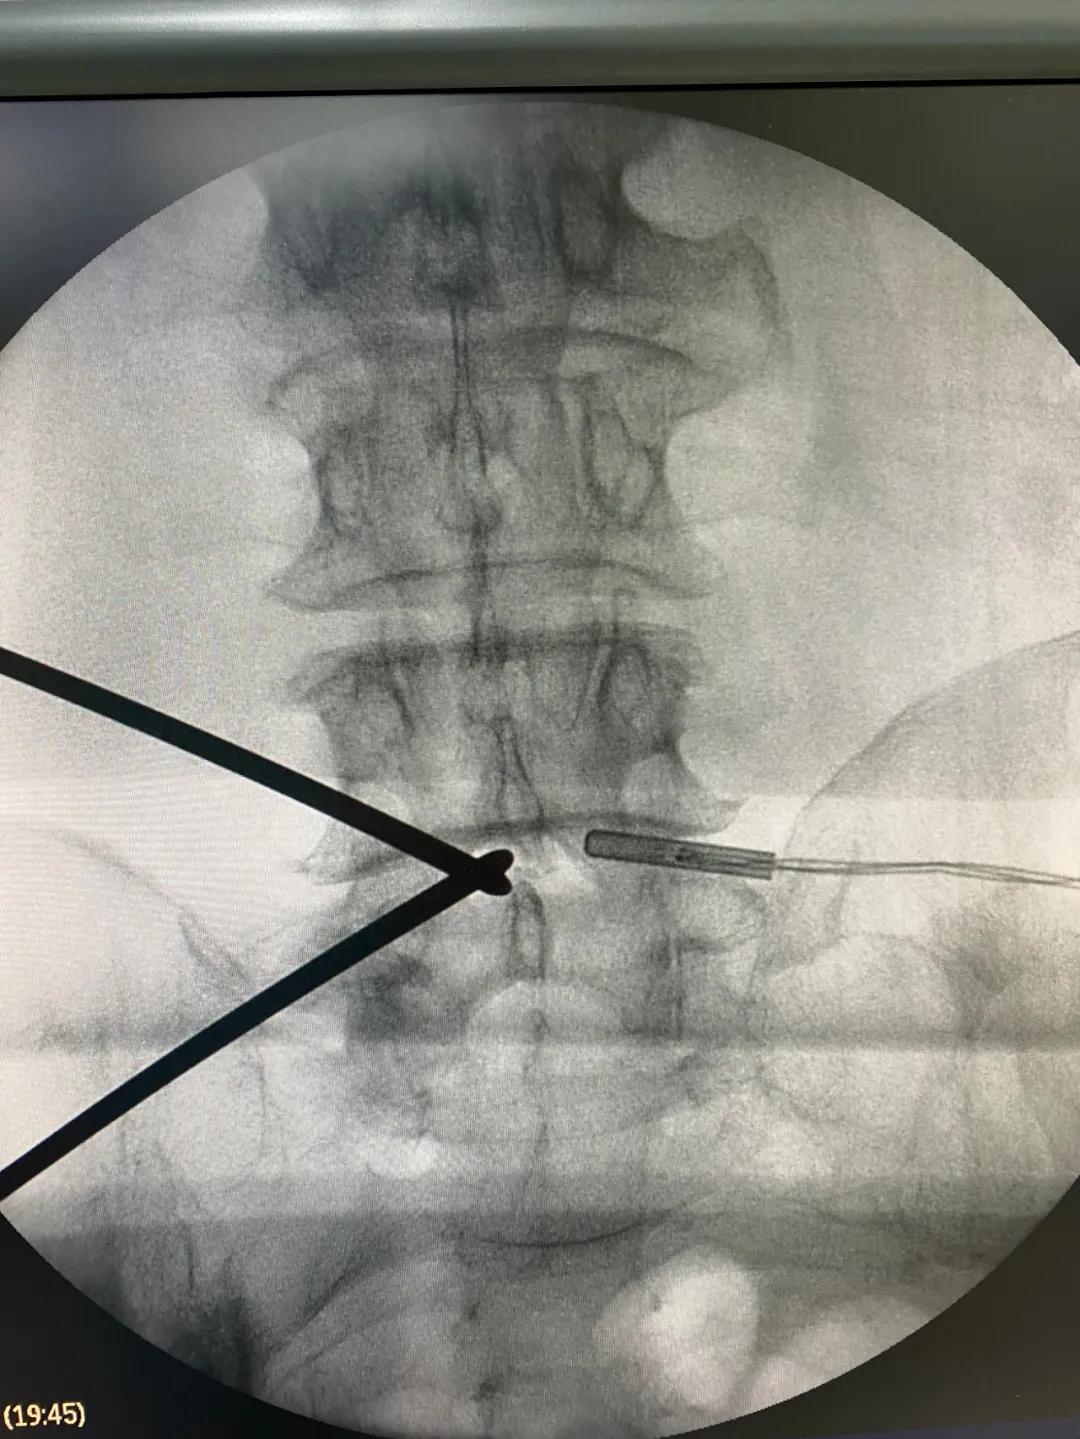

海安市中医院副院长、骨伤科主任魏爱淳主任中医师接诊后,为其制定了UBE(单侧双通道内镜微创技术)治疗方案。做好各项术前准备后,魏爱淳副院长、蒋剑锋主任和他们的手术团队在专家指导下,采用UBE专用综合器械包和专用等离子射频手术系统,成功为患者实施了UBE技术下L3/4椎管减压,L4/5椎管减压、椎间植骨融合术,手术只有5个微创小切口,术后江先生的双下肢疼痛、麻木症状缓解,手术达到预期的效果,获得了患者及家属的一致称赞。

据了解,相比传统的单通道椎间孔镜技术,UBE技术的手术视野和操作空间更广泛,适用于多种类型的腰椎间盘突出症、椎管狭窄症及轻度的腰椎滑脱症,是一项新兴的脊柱微创技术,术中清晰的镜下视野,配合熟练的器械操作,使得椎管减压和椎间融合过程在少剥离、少出血、高效率的条件下顺利完成。